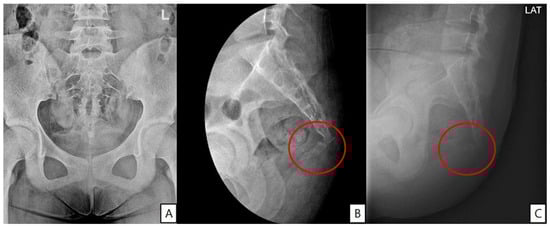

A 14-year-old girl developed coccygeal pain following a fall inside a bus six months earlier. At that time, she was diagnosed with sacrococcygeal dislocation at an outside hospital and was prescribed acetaminophen and NSAIDs, which maintained her symptoms at a Numerical Rating Scale (NRS) score of approximately 3. However, one month prior to presentation, she sustained a second fall to the same area, after which her pain worsened despite continued pharmacologic treatment, reaching an NRS score of 6. She was therefore referred to our pain clinic. The radiographs obtained at the time of the initial injury were unavailable. Radiography performed at our institution demonstrated anterior angulation of the coccyx (Figure 1). Physical examination revealed tenderness over the sacrum and coccyx. The patient was able to sit but could not remain seated for prolonged periods due to pain and reported worsening pain upon standing. No cutaneous abnormalities or swelling were noted over the coccygeal region. She denied defecation-related pain. For pain control, an ultrasound-guided caudal epidural block was performed (Figure 2). Prior to the procedure, the patient and guardians received a detailed explanation of the block. As the patient was cooperative and fully understood the process, the procedure was performed without sedation or anxiolysis, using verbal reassurance alone. Under sterile conditions, the patient was positioned prone, and the sacral hiatus was identified using ultrasound. After local anesthesia of the skin at the needle insertion site, a butterfly catheter was advanced toward the sacral hiatus under an out-of-plane view, traversing the sacrococcygeal ligament. The needle was then redirected in-plane into the epidural space. A mixture of 1 mL of 2% mepivacaine, 8 mL of 0.9% normal saline, and 5 mg of dexamethasone was injected. At the 2-week follow-up, although the qualitative character of pain remained similar, the patient reported an increased ability to remain seated and a reduced frequency of pain when standing. Her pain intensity decreased significantly to an NRS score of 2, accompanied by noticeable functional improvement. At the 2-month follow-up, her pain remained at an NRS score of 2, and she maintained a level of daily functioning without significant limitations.

Figure 1. (A) Anteroposterior pelvic radiograph showing no visible fracture but overall coccygeal axis deviation. (B) Dynamic lateral view showing anterior angulation of the coccyx at the sacrococcygeal junction (red circle). (C) Seated lateral view demonstrating accentuated anterior displacement, suggestive of coccygeal instability (red circle).